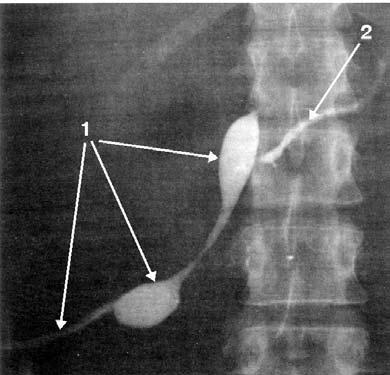

Рис. 167. Фистулограмма. Наружный терминальный свищ поджелудочной железы. 1 – свищевой ход; 2 – панкреатический проток в дистальной части ПЖ

Рис. 168. Фистулограмма. Наружный боковой свищ поджелудочной железы.

1 – в свищевой ход введена трубка; 2 – панкреатический проток прослеживается на всем протяжении и контрастное вещество свободно проходит в 12ПК

Для уточнения диагноза, а также для определения калибра и направления свищевого хода обычно применяется фистулография (см. рис. 167, 168). Количество жидкости, вытекающей через свищ, должно учитываться и отражаться в истории болезни. Бывает целесообразным также лабораторный анализ отделяемого (определение ферментов поджелудочной железы, цитологическое исследование осадка и т. д.).